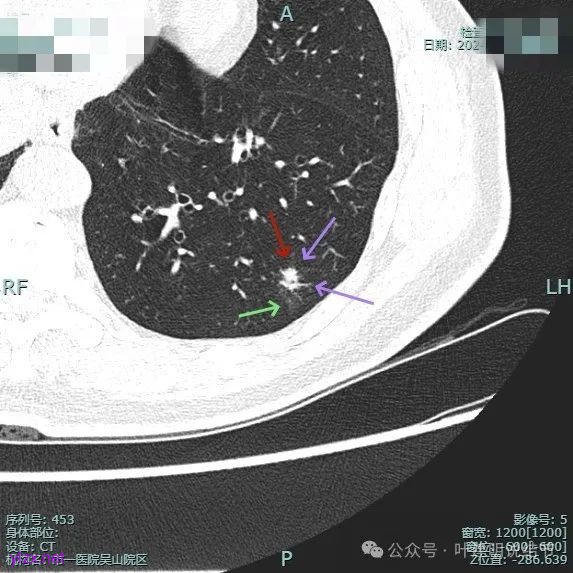

再看2024年10月时复查时我的意见:

对比至少没有进展,密度似略减低,考虑慢性炎伴纤维增生可能性大。

再看2025年4月初复查的情况:

整体纵向仍偏长条些,实性部分不太致密,边上磨玻璃成分的轮廓与界限不太清楚,毛刺显得长。

仍有支气管扩张,但较2024年时密度感觉低了点。

密度较淡且缺乏收缩力。

密度杂乱,血管进入,但血管说不上明显异常增粗,磨玻璃成分淡而瘤肺界限欠清。

总体较之前密度有减低,缺乏聚拢性。